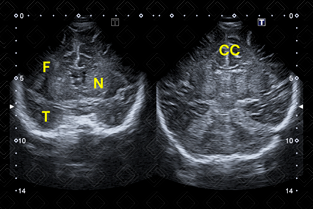

As imagens rotineiramente são obtidas nos planos coronal e sagital. As imagens coronais são obtidas colocando-se o transdutor transversamente pela fontanela anterior e angulando o feixe de ultrassom da frente para trás. As imagens sagitais são obtidas posicionando-se o transdutor em orientação longitudinal na fontanela anterior e angulando o feixe do meio para lateral (figuras 1 a 6).

Descrição das figuras 1 e 2: Ultrassonografia transfontanela cortes coronais, realizada varredura de anterior para posterior. CC – corpo caloso; Ch – plexo coroide; [cms-watermark] F – lobo frontal; N – núcleos da base; [cms-watermark] T – lobo temporal.